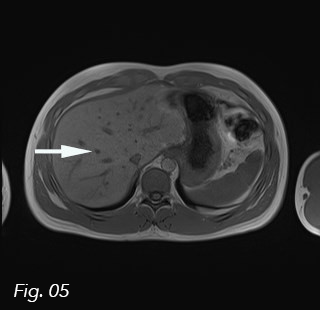

Fig. 4: Axial T2 weighted image. The liver parenchyma appears homogeneous and isointense.